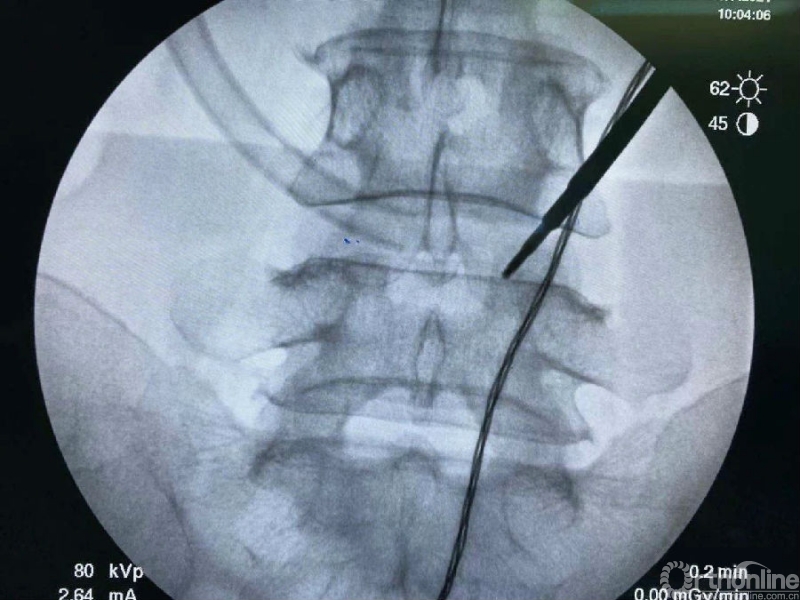

术前克氏针确定内镜口位置位于椎板稍微偏远,是一个比较理想的定位。

然后建立通道。